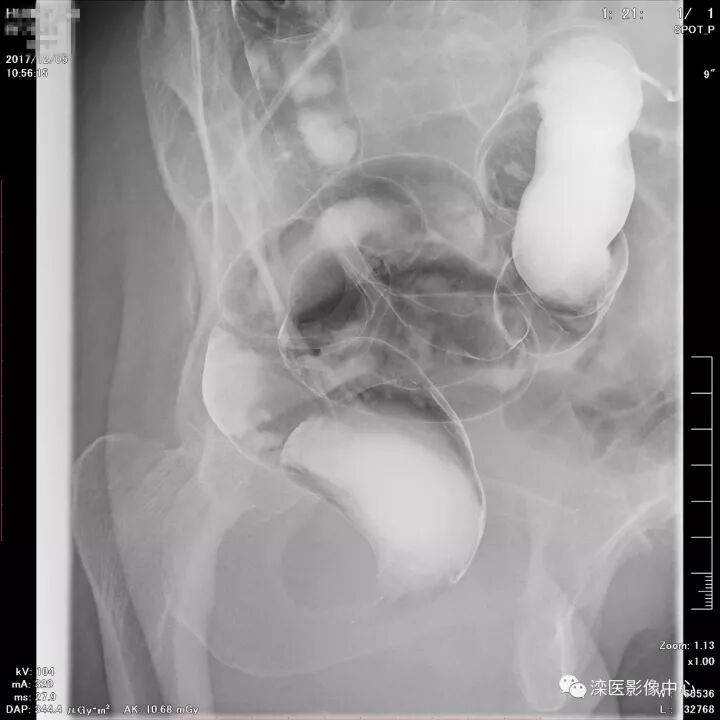

下面请您审阅近期我院影像科开展下消化道双对比造影检查的图像:

(以上图像是对显示降结肠的显示